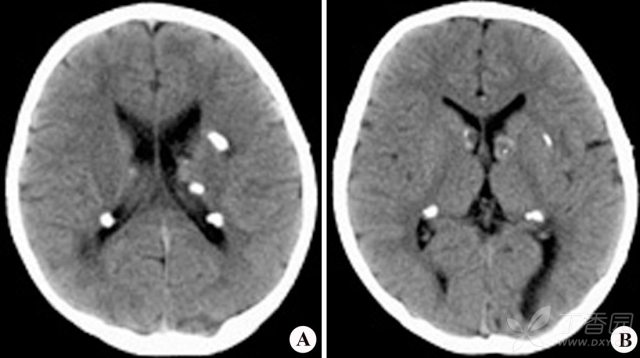

影像学上可表现为室管膜下多发结节(90%),皮质及皮质下结节(70%),脑白质异常信号和室管膜下巨细胞星形细胞瘤。室管膜下多发结节常发生于尾状核的表面,位于室管膜下,呈对称或不对称分布。T1WI 多呈等或稍高信号;T2WI 及 FLAIR 呈高信号,钙化则成低信号。增强扫描结节多强化。CT 可见典型「烛泪征」。皮质及皮质下结节 T1WI 可见结节样增厚的脑回,呈稍低信号;T2WI/FLAIR 呈高信号。增强多不强化。脑白质异常典型者可表现为「辐射带征」,即从脑室或脑室旁白质延伸至正常皮层或皮层下结节。室管膜下巨细胞星形细胞瘤为较罕见的中枢神经系统肿瘤。T1WI 呈等信号或低信号,T2WI 呈轻度至明显高信号,钙化区呈低信号。增强扫描瘤体呈明显均匀强化。可出现一侧或双侧脑室积水。

图 4:CT 烛泪征,即沿侧脑室的钙化灶